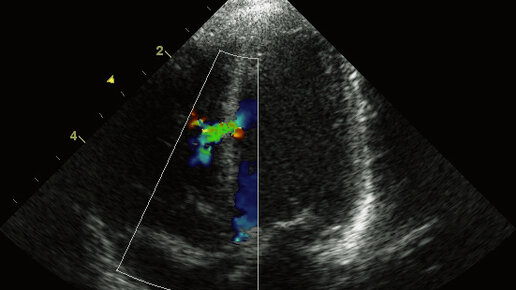

ДМЖП - пугающая аббревиатура для каждой беременной

Впервые увидела такой диагноз на узи во время второго скрининга. Это было примерно на девятнадцатой неделе беременности. У меня нет медицинского образования, поэтому мне для понимания нужно объяснять все медицинские нюансы простым языком. Но врач узи оказалась не слишком словоохотливой. Поэтому о том, что ДМЖП - дефект межжелудочковой перегородки, я узнала только позже из интернета. От того, что объяснений было мало, становилось ещё более тревожно. Вообще, всё, что касается детей, всегда очень волнительно для мамы...